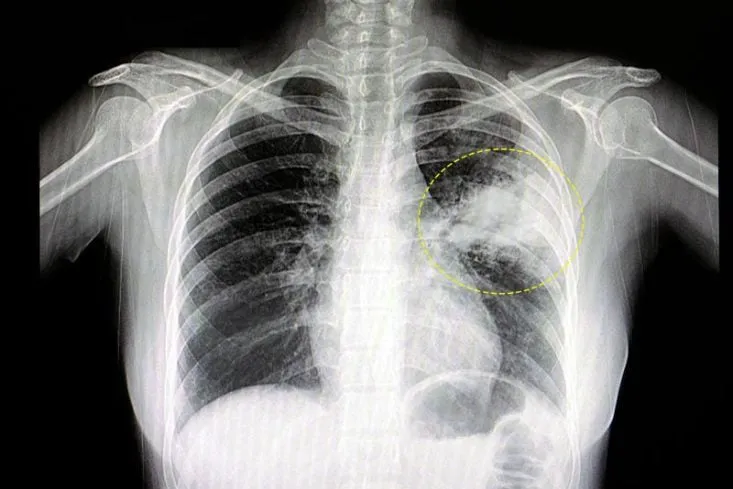

El Ministerio de Salud Pública insta a grupos de riesgo a vacunarse contra la gripe y contra el Virus Sincicial Respiratorio (VSR) en toda la provincia debido al incremento de casos registrados en las últimas semanas. Las autoridades sanitarias instan a la población a vacunarse, especialmente a los grupos de riesgo, para prevenir complicaciones graves.

Vacunación contra el Virus Sincicial Respiratorio (VSR) :

Embarazadas: Se aplica una dosis única entre las semanas 32 y 36 de gestación para proteger al recién nacido contra el VSR, un virus que causa infecciones respiratorias graves en bebés y niños pequeños.

El Ministerio de Salud Pública recuerda que la vacunación es la forma más efectiva de prevenir estas enfermedades y sus complicaciones.